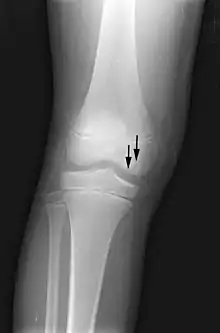

X-ray images of avascular necrosis in the early stages usually appear normal. In later stages it appears relatively more radio-opaque due to the nearby living bone becoming resorbed secondary to reactive hyperemia.[2] The necrotic bone itself does not show increased radiographic opacity, as dead bone cannot undergo bone resorption which is carried out by living osteoclasts.[2] Late radiographic signs also include a radiolucency area following the collapse of subchondral bone (crescent sign) and ringed regions of radiodensity resulting from saponification and calcification of marrow fat following medullary infarcts.

Radiography of avascular necrosis of left femoral head. Man of 45 years with AIDS.